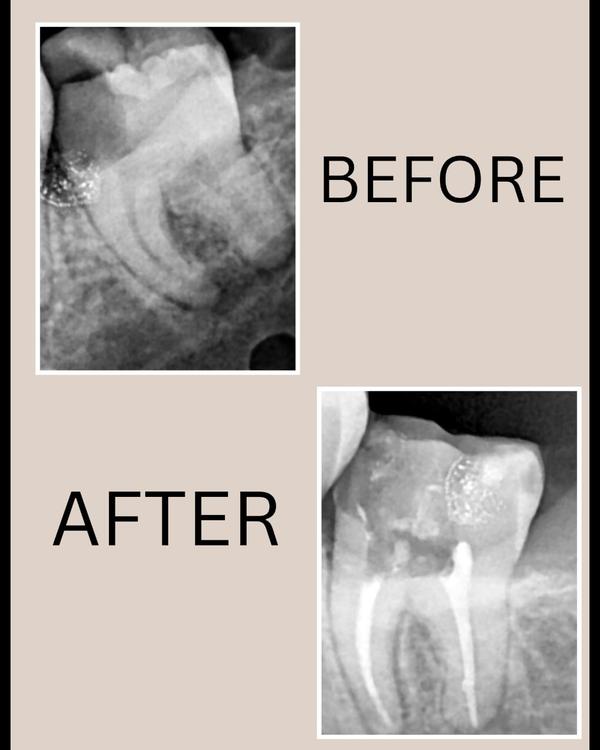

specialisation in Root Canal Treatment

ROOT CANAL TREATMENT IN THANE